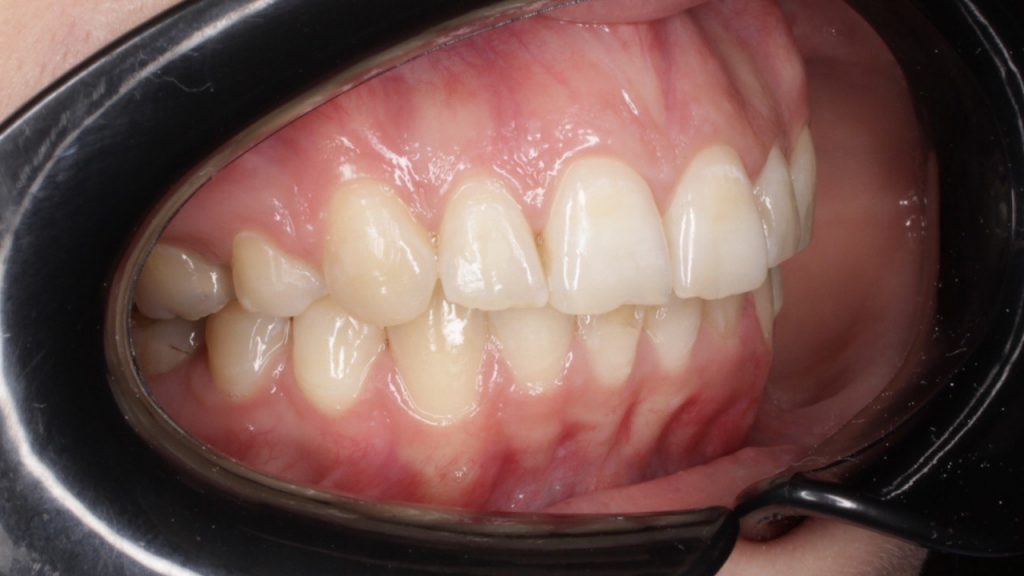

Портфолио - после 1